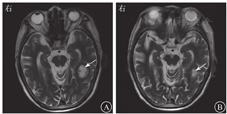

患者男,79岁,因"咳嗽、咳痰8 d,发热3 d"于2020年9月7日收入南京中医药大学附属南京中医院感染性疾病科。患者8 d前无明显诱因出现阵发性咳嗽、咳痰,痰色黄、质黏、难以咳出,伴气喘。3 d前,患者出现发热,最高体温达38.4 ℃,伴大小便失禁及呕吐胃内容物1次,至南京中医药大学附属南京中医院急诊科就诊。查血常规示白细胞计数为23.70×109/L,中性粒细胞比例为0.913,血红蛋白为134 g/L,血小板计数为210×109/L,CRP为73 mg/L。胸部CT检查示两肺气肿伴肺大疱形成,两肺间质性改变;左肺上叶团片影,考虑炎性病灶可能(图1A)。患者既往有心房颤动、心功能不全、慢性阻塞性肺疾病病史;有未分化结缔组织病病史1年余,长期服用泼尼松和雷公藤,泼尼松用量为5 mg/次,2次/d。入院后体格检查:体温为36.5 ℃,心率为75次/min,呼吸为20次/min,血压为98/62 mmHg(1 mmHg=0.133 kPa)。神志清楚,精神萎靡,淋巴结未及肿大。桶状胸,双肺呼吸音减弱,双下肺可闻及少量细湿啰音。心律不齐,未闻及病理性杂音。腹软,无压痛及反跳痛。双下肢无水肿。实验室检查示CRP为160 mg/L;ESR为102 mm/1 h;降钙素原为11.54 μg/L;脑钠肽为2 684 ng/L;铁蛋白>1 650 μg/L;白蛋白为19 g/L;EB病毒、CMV、β-D-葡聚糖试验、半乳甘露聚糖抗原试验、T细胞亚群、免疫五项(IgA、IgG、IgM、补体C3、补体C4)检查、T-SPOT.TB和PPD结果均为阴性。一般细菌痰涂片、痰涂片找抗酸杆菌、真菌涂片检查结果均为阴性。结合既往病史、辅助检查,考虑肺部细菌、真菌感染均不能排除,故予比阿培南(300 mg/次,4次/d)联合伏立康唑(200 mg/次,2次/d)静脉滴注抗感染治疗。9月14日(入院第8天)患者体温恢复正常,咳嗽、咳痰较前好转,胸部CT检查示肺部病灶较前吸收(图1B),血培养结果为乔治教堂诺卡菌阳性(图2),加用复方磺胺甲噁唑(磺胺甲噁唑/甲氧苄啶,800 mg/160 mg, 2次/d)。9月18日完善腹部和头颅MRI检查,结果回报左侧颞叶异常信号,考虑脓肿可能(图3A),余脏器未见血行播散病灶。患者感染乔治教堂诺卡菌,血行播散至脑形成脓肿,播散性诺卡菌病诊断明确,改用头孢曲松(2 g/次,2次/d)静脉滴注联合复方磺胺甲噁唑(2次/d)口服抗感染治疗1周后复查,血常规示白细胞计数为5.90×109/L,中性粒细胞比例为0.821,CRP<1 mg/L。患者临床症状和炎症指标较前明显好转,9月30日出院后序贯口服复方磺胺甲噁唑(2次/d)联合利奈唑胺(600 mg/次,2次/d),治疗10 d后复查血培养结果为阴性,10月14日复查头颅MRI示脑脓肿较前吸收(图3B)。10月27日复查头颅CT,提示病灶较前明显好转(图4)。2021年2月19日患者复查血培养结果为阴性,胸部CT检查示病灶较前吸收(图1C),头颅MRI检查示病灶已吸收完全,予复方磺胺甲噁唑减量(磺胺甲噁唑/甲氧苄啶,400 mg/80 mg, 3次/d)。